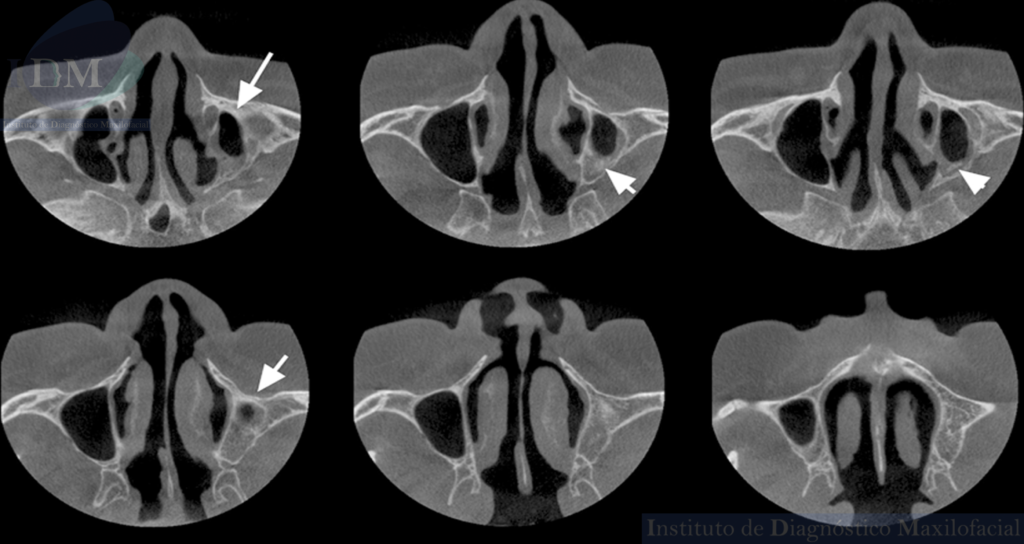

A la evaluación de la tomografía computarizada de haz cónico de campo mediano se observa la disminución de la longitud cefalo caudal y antero posterior del seno maxilar del lado izquierdo en comparación a su contralateral (visto en los cortes coronales y axiales respectivamente).

Asimismo, se observa el engrosamiento de la mucosa antral a predominio de la pared posterior que a su vez presenta una imagen hiperdensa de forma irregular compatible con probable Antrolito. Finalmente, en zonas edéntulas de premolares y molares del segundo cuadrante se observa el trabeculado óseo característico del maxilar superior que debería estar ocupado por el seno maxilar.

CORTES AXIALES